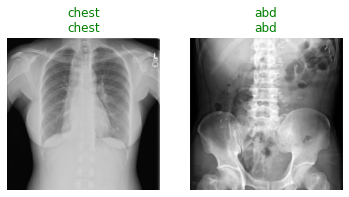

When you run the following cell, the first line shows the groundtruth for whether the radiograph is of the chest or abdomen. The second line is the model prediction for whether the image is a chest or abdominal radiograph.

test_files = get_image_files(path/'test')

test_dl = learn.dls.test_dl(test_files, with_labels=True)

learn.show_results(dl=test_dl)